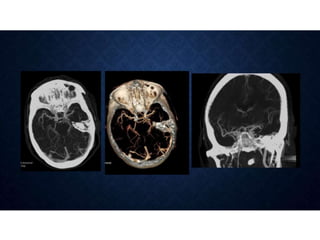

 Color-coded perfusion maps of cerebral blood volume,

cerebral blood flow, and mean transit time are then generated

at the workstation

PERFUSED-BLOOD-VOLUME MAPPING

• Unenhanced CT followed by CT angiography of the brain can be used to assess arterial

patency and tissue perfusion during the infusion of a single bolus of contrast.

• Cerebral blood volume values are obtained by subtracting the unenhanced CT image data

from the CT angiographic source image data.

• Degree of parenchymal enhancement depends on the actual cerebral blood volume and the

quantity of contrast material reaching the tissue during the image acquisition - the

subtracted images are referred to as perfused-blood- volume maps.

• Can depict entire brain parenchyma, however cannot quantitate CBF and MTT.